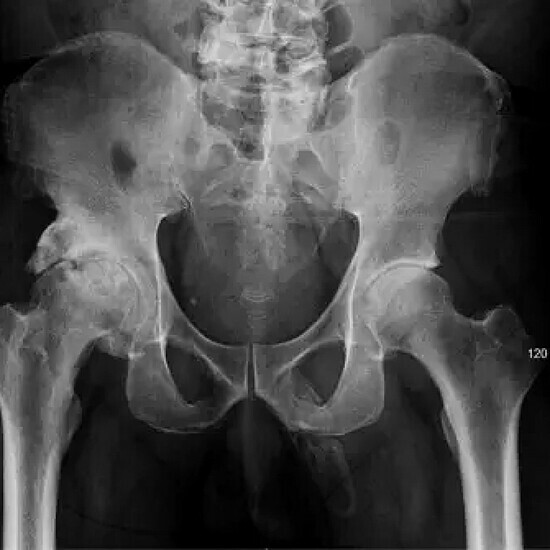

‘Hóa thạch’ dương vật

Đến viện khám do đau đầu gối, người đàn ông Mỹ 63 tuổi phát hiện có tế bào xương hình thành trong dương vật, dần hóa thạch bộ phận này, các mô mềm bị vôi hóa và cứng lại. Đây là trường hợp cực kỳ hiếm gặp, trong lịch sử y khoa mới ghi nhận gần 40 ca bệnh tương tự.

Ca bệnh được công bố trên tạp chí Urology Case Reports hồi tháng 9.

Phim chụp X-quang của bệnh nhân. Ảnh: Urology Case Reports